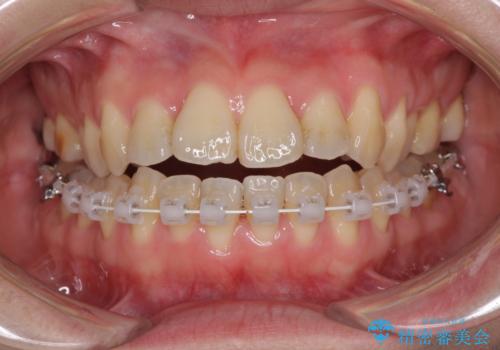

ハーフリンガル 反対咬合の改善

- ハーフリンガル

目立ちにくい装置での治療をご希望とのことで、上顎が裏側装置、下顎が表側装置のハーフリンガルにより矯正治療を行うこととしました。

下顎左右の奥にアンカーボルトを使用して、無理のない範囲で後方に移動させ、きれいに仕上げることができました。